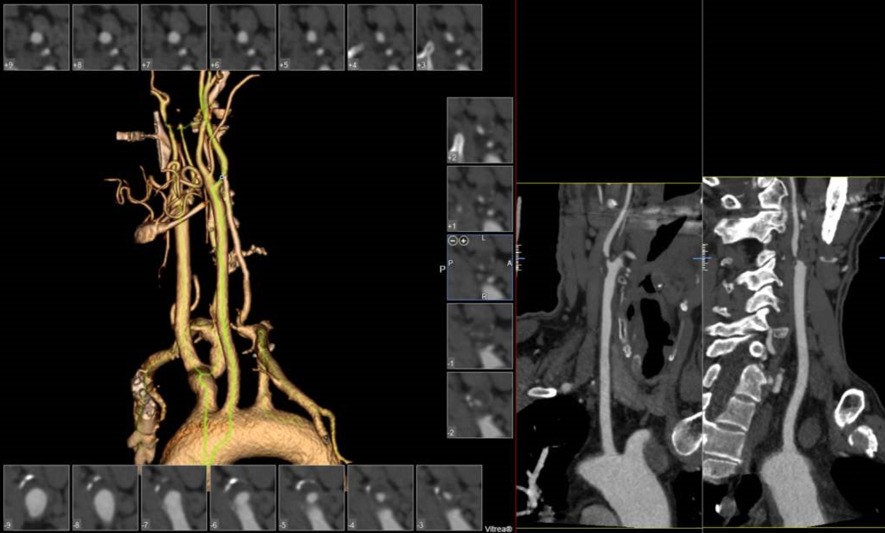

病例3:62岁男性,发作性胸痛9个月,外院行PCI后仍有症状,拟冠脉搭桥前发现双侧颈动脉狭窄,行双侧CAS,先右后左,3个月后行左侧CAS,术后复查彩超显示支架通畅,1个月后行冠脉搭桥手术。

右侧术前

右侧术后

左侧术前

左侧术后